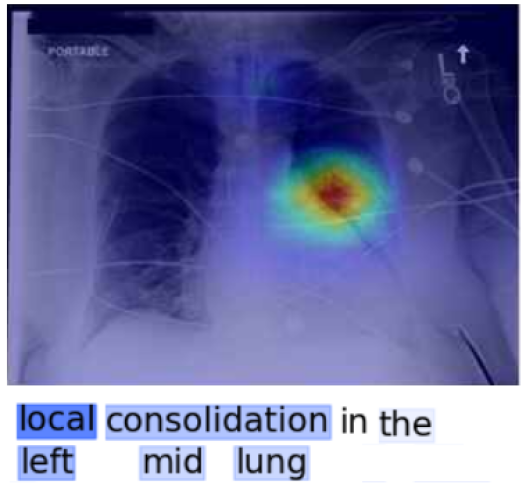

We propose MATEX (Multi-scale Attention and Text-guided Explainability), a novel framework designed to bridge this gap. MATEX generates anatomically faithful and text-aware attribution maps by leveraging three core innovations: (1) a multi-scale attention rollout strategy to capture signal flow across transformer layers, (2) clinically informed spatial priors derived from radiological text, and (3) a layer consistency mechanism to filter out unstable gradients. In this sense, MATEX serves as an interpretability framework for large vision–language models in medical imaging, analogous to the role of M2IB in explaining multimodal reasoning. As shown in Figure 1, MATEX provides joint visual–textual explanations by localizing lung cancer regions through anatomically consistent heatmaps while simultaneously highlighting the caption keywords that guide these attributions. This alignment between image evidence and clinical language enables transparent inspection of LVLM decision-making, closely reflecting radiologist-style reasoning and facilitating trustworthy deployment in medical settings.

Figure 3 shows a qualitative comparison between MATEX and M2IB on the MS-CXR dataset. Each column depicts a clinical case, with MATEX heatmaps on the top row and M2IB results below, visualized as overlayed attribution maps on chest X-rays.

Figure 3 illustrates that MATEX offers several consistent improvements over M2IB. Across all evaluated cases, MATEX produces heatmaps with sharper localization and tighter alignment to pathological regions, enhancing anatomical coherence. In scenarios involving bilateral or multi-zone findings—such as lower lobe consolidation—MATEX accurately captures both affected zones while avoiding overspill, whereas M2IB often yields diffuse attention. Additionally, MATEX exhibits improved boundary adherence, particularly in cases of opacification, which enhances interpretability for clinical use. It also demonstrates reduced noise activation by limiting attribution to relevant structures, unlike M2IB, which sometimes highlights unrelated areas.

These improvements are attributable to MATEX’s ability to produce more anatomically precise and clinically aligned explanations. The framework effectively captures multi-region pathologies without spatial drift and maintains clear boundaries around relevant findings.